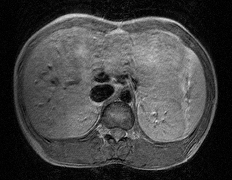

私の胸のMRI(磁気共鳴画像)

画像上が胸、下が背中。